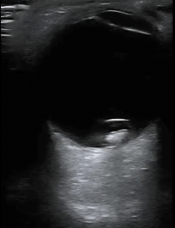

A 78 yo M presents to the ED with a chief complaint of blurry vision. Gepost op 25 november 201725 november 2017 door netwerkvsseh What’s the Diagnosis? @emdaily.cooperhealth.org Dit delen: Delen op X (Opent in een nieuw venster) X Share op Facebook (Opent in een nieuw venster) Facebook Delen op LinkedIn (Opent in een nieuw venster) LinkedIn E-mail een link naar een vriend (Opent in een nieuw venster) E-mail Afdrukken (Opent in een nieuw venster) Print Vind-ik-leuk Aan het laden... Gerelateerd